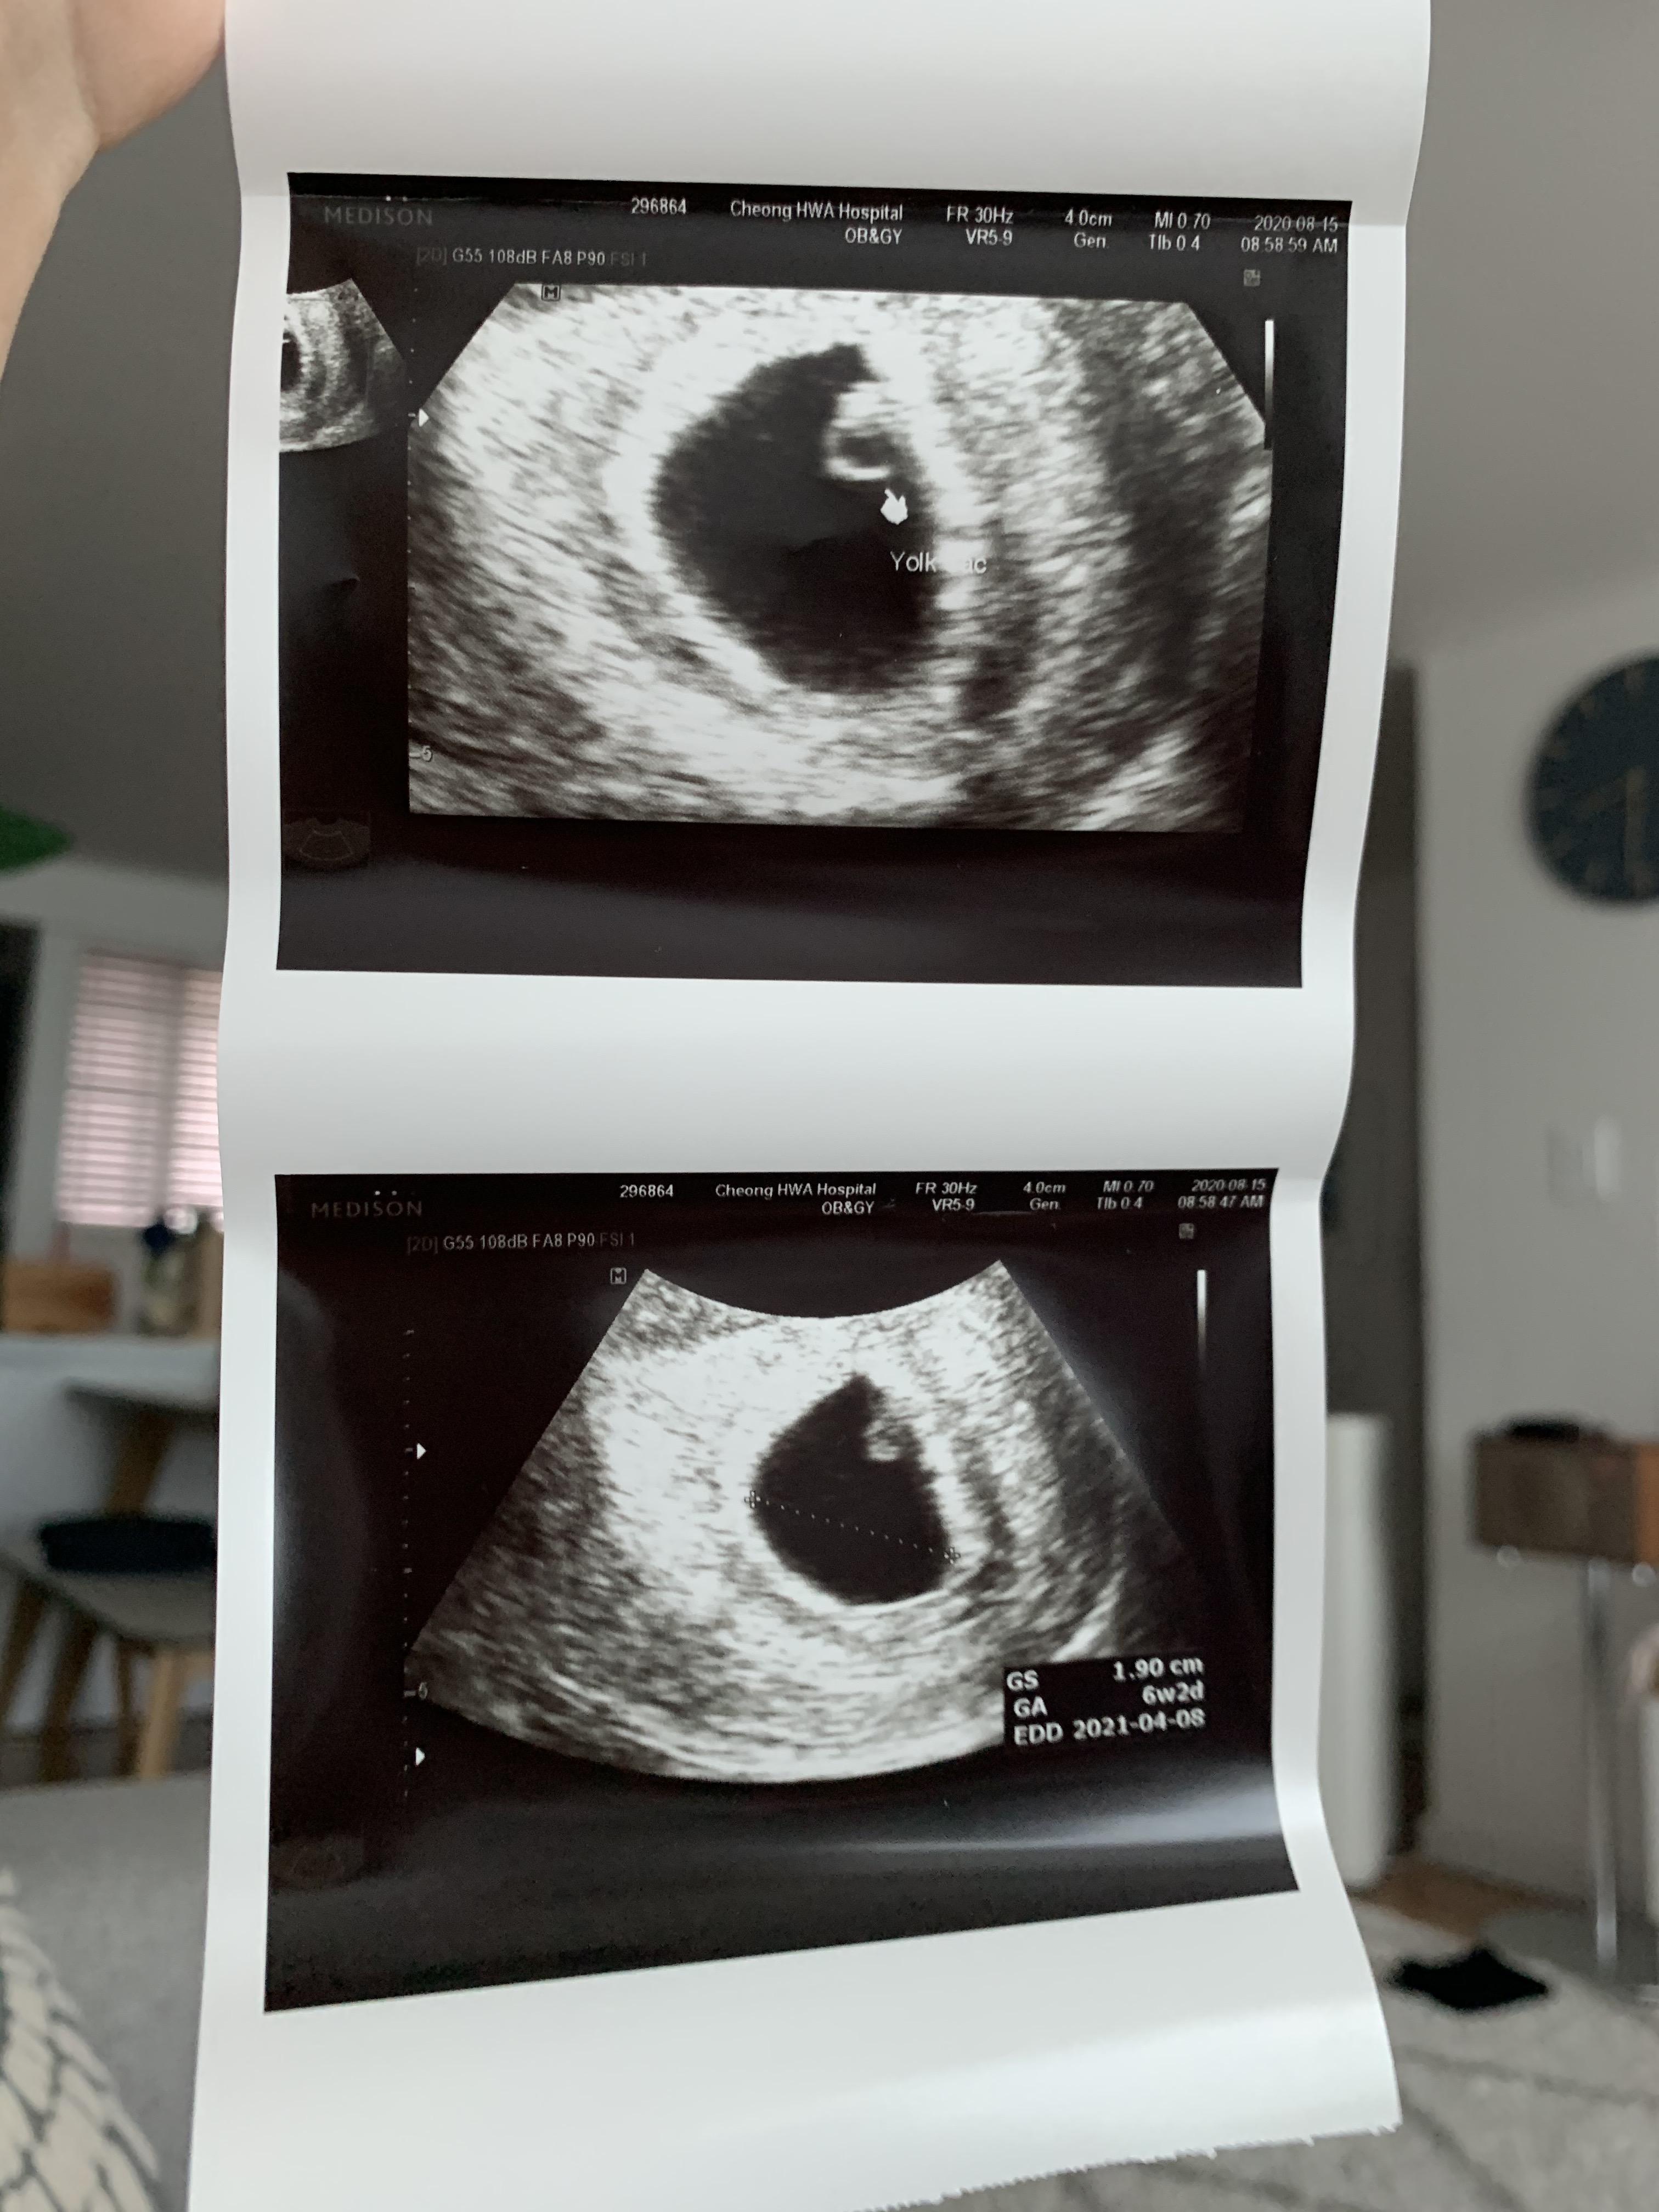

두둥!

난황에 배아까지 봅니다!

게다가 반짝반짝 심장소리까지 들었어요!

아기집은 두 배로 커져서 2센티 정도 되고,

아기 크기가 0.5cm정도 되더라고요.

다들 난황보면 다이아몬드 반지같다고 하는데,

엄청 큰 아기가 다이아몬드처럼 반짝반짝해요.